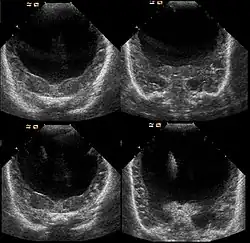

Die Diagnose kann vorgeburtlich im Rahmen von Pränataldiagnostik durch insbesondere Feinultraschalluntersuchungen im zweiten Trimenon, teils aber auch schon früher, gestellt werden. Während die Feststellung der alobären und der semilobären Form oft recht einfach ist, ist die der lobären Holoprosencephalie komplizierter.

Nachgeburtlich sind die Schnittbildverfahren Sonographie und Magnetresonanztomographie Methoden der Wahl.[19]